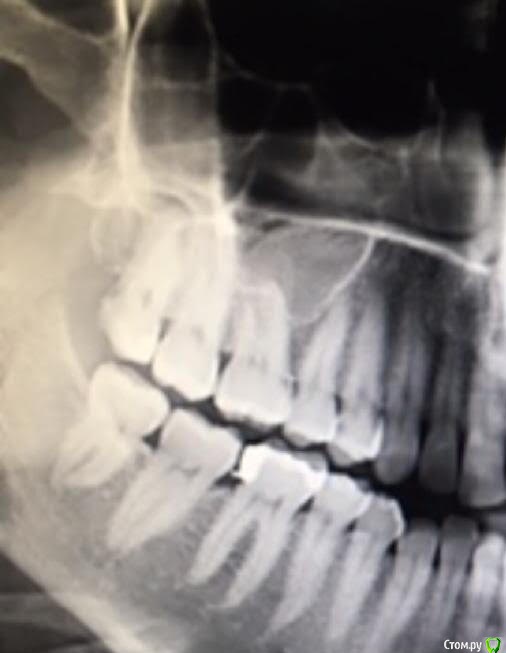

It'sGeorgy Опубликовано 30 мая, 2020 Поделиться Опубликовано 30 мая, 2020 (изменено) Подниму тему, чтобы лишний раз не создавать.Подскажите пожалуйста, вчера впервые столкнулся с новым для себя строением верхних восьмерок. Снимок беды не предвящал. На практике оказались небный и сросшиеся щечные. Апекс небного выраженно загнут щечного, апекс щечного загнут небно, между этими загибами 2-3 мм. костной ткани. Попытался изначально покачать элеватором - почти ноль эффекта. Взял щипцы, попробовал вестибулярно качнуть - так же ноль эффекта. Распилил по горизонтали, элеватор в распил, крутанул - хрусть получен. Взял иглодержатель, проверил, разделены ли до конца корни - разделены, можно было немного пошатать каждый раздельно, трещина уходящая вглубь фуркации так же визуализировалась. А вот в дальнейшем у меня ушло минут 40 для того, чтобы вытащить эти корни, ибо они как стояли намертво до распила по фуркации, так и остались стоять после него. Вытащил апексы путем выпиливания кости вокруг, предварительно отломав процентов 70 от длинны корней. Спасибо моей пациентке, что на протяжении часа с лишним могла держать широко рот и моему налобнику, который в тяжелой ситуации помог сохранить визуализацию, без этого совсем тяжко было бы. Вопрос такой: что делать, с такими зубами, когда ты уже фрагментировал корни, а они все еще неподвижны? Сразу пилить вокруг? Или был шанс их вывихнуть без выпиливания и у меня просто не получилось? Изменено 30 мая, 2020 пользователем It'sGeorgy 1 Ссылка на комментарий

kramer Опубликовано 30 мая, 2020 Поделиться Опубликовано 30 мая, 2020 всегда помогает?Как правило. Очевидно, что верхние 8 почти всегда удаляются быстро. Если по-быстрому не получается, надо прикинуть, в чем может быть причина. Либо это многокорневой зуб, либо загнутые корни, либо мощный бугор (как на вашем снимке), либо комбо. Резекция кости вестибулярно и дистально по крайней мере создаст пространство для вывихивания Ссылка на комментарий